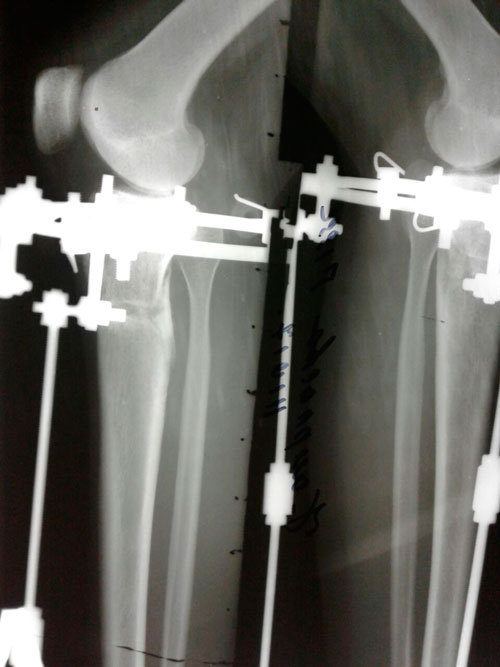

Исходник - 24 года.

2-я ротация.

Дата операции 19.07.2017г.

Дата операции 19.07.2017г

Дата снятия аппаратов 17.10.2017г.

Срок лечения 88 дней.